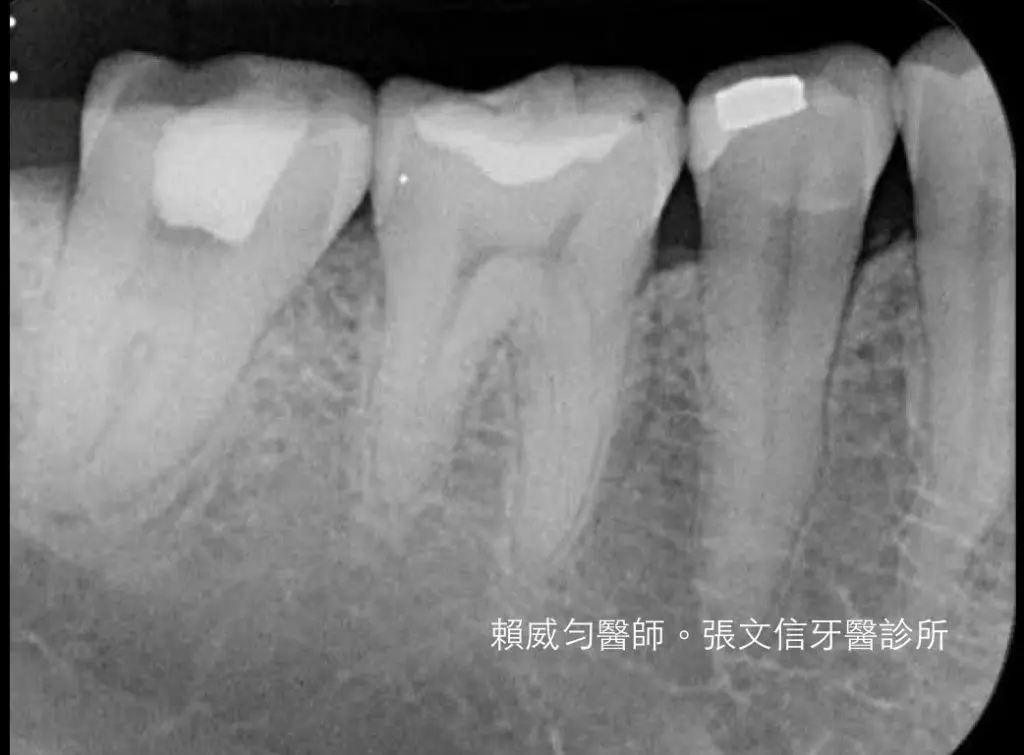

C-形根管是根管治療中大家都會遇到的困難案例。

C-形根管的開口多變,X光片的特徵容易讓人混淆,根管內部結構複雜,死角眾多。

一打開牙齒,根管邊界無法辨認,全部都連成一氣。醫師從哪個方位入手都不對。插了根管銼針,X光裡,銼針是直直地從正中央貫穿牙齒,看了都讓人膽戰心驚。